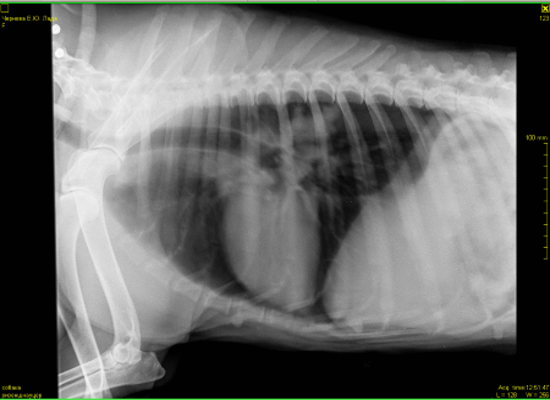

Всем доброго дня.Наши последние сводки с фронтов.В субботу мы сделали рентген.В программе,когда врач нам объяснял ситуацию,конечно было все более наглядно.Сейчас я не совсем понимаю,почему именно эти снимки открыты для доступа и почему именно их он записал.По словам врача у нас есть все ж изменения в области средостения в лимфаузлах. Что-то давит на пищевод.На снимке он должен быть прямой ,а он немного изогнут. Увеличено с одной стороны сердце и есть затемнения в легких справа(врач заметил именно затемнения,а не образования).По мне так совершенно ничего не понятно,а только больше вопросов возникло у меня.Нам назначили УЗИ и посещение кардиолога.Отсюда вопрос.Есть ли у кого ценный врач-кардиолог в районе СВАО? Операция по прежнему под ОЧЕНЬ большим вопросом.Лада пьет лекарства.Немного вялая от них.Гуляет ,кушает,спит и играет в мячик.Кашляет.

В легких безусловно что то есть.... вопрос что.

Сердце по рентгену не увеличено, у него " сглажена талия", что может быть при перегрузке правого сердца, которое отвечает за легкие . Повышено внутрилегочное давление из за mts в лимфоузлах скорее всего корня легких. Возможно начинает скапливаться жидкость в перекарде, а может все вместе. Мы никак не сможем на все это повлиять. Для всего, что я описала нужно не просто увидите жидкость в перекарде, а померить давление на лёгочной артерии, доплер на узи аппарате нужен. В принципе, что хотели узнать - есть там что то или артефакт. Есть(((. Грядку оперировать? Считаю, что операция только усугубит страдания. Все таки я за антибиотик и дексаметазон, и посмотреть. Клинически может уменьшиться кашель.